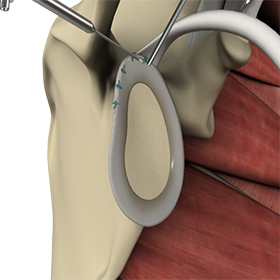

Shoulder Stabilization with Labral Repair

Shoulder instability is a chronic condition that causes frequent dislocation of the shoulder joint. A dislocation occurs when the end of the humerus (the ball portion) partially or completely dislocates from the glenoid (the socket portion) of the shoulder. A partial dislocation is referred to as a subluxation while a complete separation is referred to as a dislocation. The repeated dislocation of the humerus out of its socket is called chronic shoulder instability.

Labral debridement and repair is a surgical procedure to remove loose and damaged cartilage in the labrum and to secure the torn labrum to its normal attachment to the bone.

Anterior Shoulder Stabilization

Anterior shoulder stabilization is a surgical procedure performed to treat a condition called anterior shoulder instability. Anterior shoulder instability, also known as anterior glenohumeral instability, is a shoulder condition in which damage to the soft tissues or bone causes the head of the humerus (upper arm bone) to dislocate or sublux from the glenoid fossa, compromising the function of the shoulder.